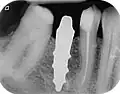

- с помощью рентгенографии изучаются качество и плотность костной ткани;

- проверяются окклюзия и артикуляция;